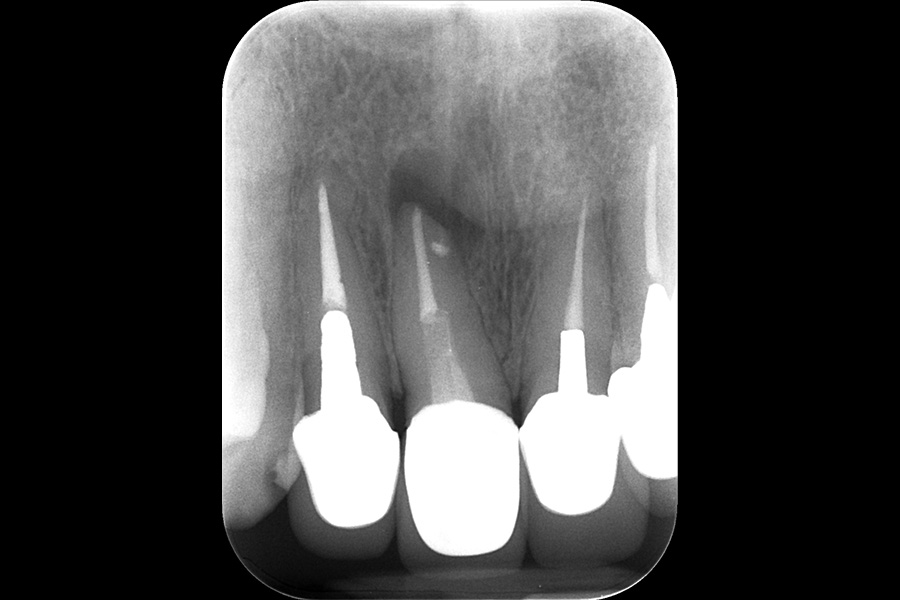

治療前